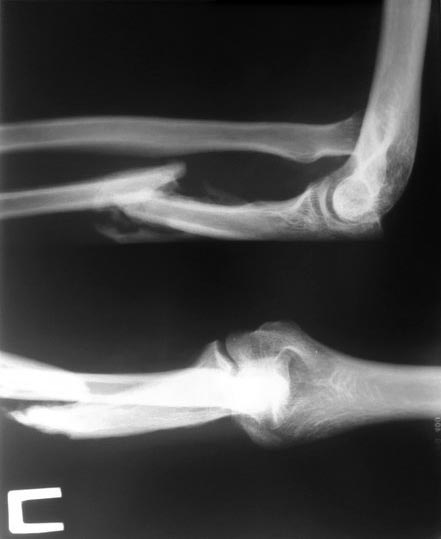

Пациентка из неблагополучной семьи получила травму в мае 2015 года , в следствии удара тупым предметом в область в/3 предплечья, за мед помощью не обращалась.

К нам обратилась через 4 месяца. По данным Ro - застарелый вывих головки лучевой кости c неверно консолидирующимся переломом в/з локтевой кости. Ваша тактика лечения . Прилагаю снимки .

Добавлю что клинически функция локтевого сустава нарушена, сгибание 30 -40 градусов , предплечье деформировано , болезненно при пальпации в проксимальном отделе .